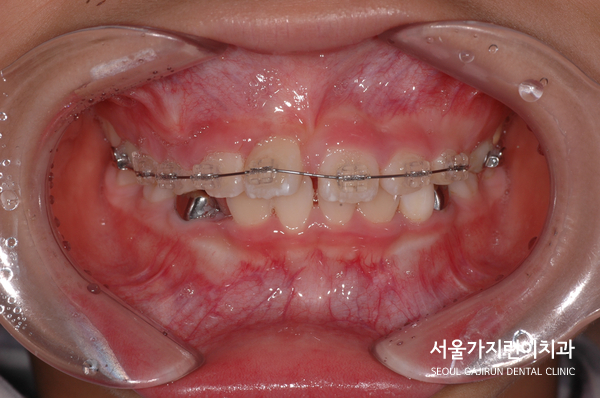

해당 환자분의 경우 8세의 남아였는데요. 앞니가 180도로 돌아간 상태로 매복된 것을 확인할 수 있었습니다. 거꾸로 숨어있던 건데요. 매복된 치아의 견인을 위해 치아에 버튼을 달고 치근 흡수를 조심하면서 아주 약한 힘으로 견인치료를 진행했습니다.

다행히 치료를 시작한 지 14개월 만에 앞니가 형태를 보이고 자리를 잡아갔는데요. 이 케이스의 경우 비교적 일찍 치아교정을 시작했다는 전제조건이 있었는데요. 매복된 치아가 잇몸뼈와 심하게 유착이 되었다면 교정력을 아무리 주어도 치아가 내려오지 않을 가능성이 있었습니다. 그렇기 때문에 상악 중절치의 매복을 비롯한 치아 맹출 장애는 치아교정전문치과에서 진료를 받아야 하는데요.